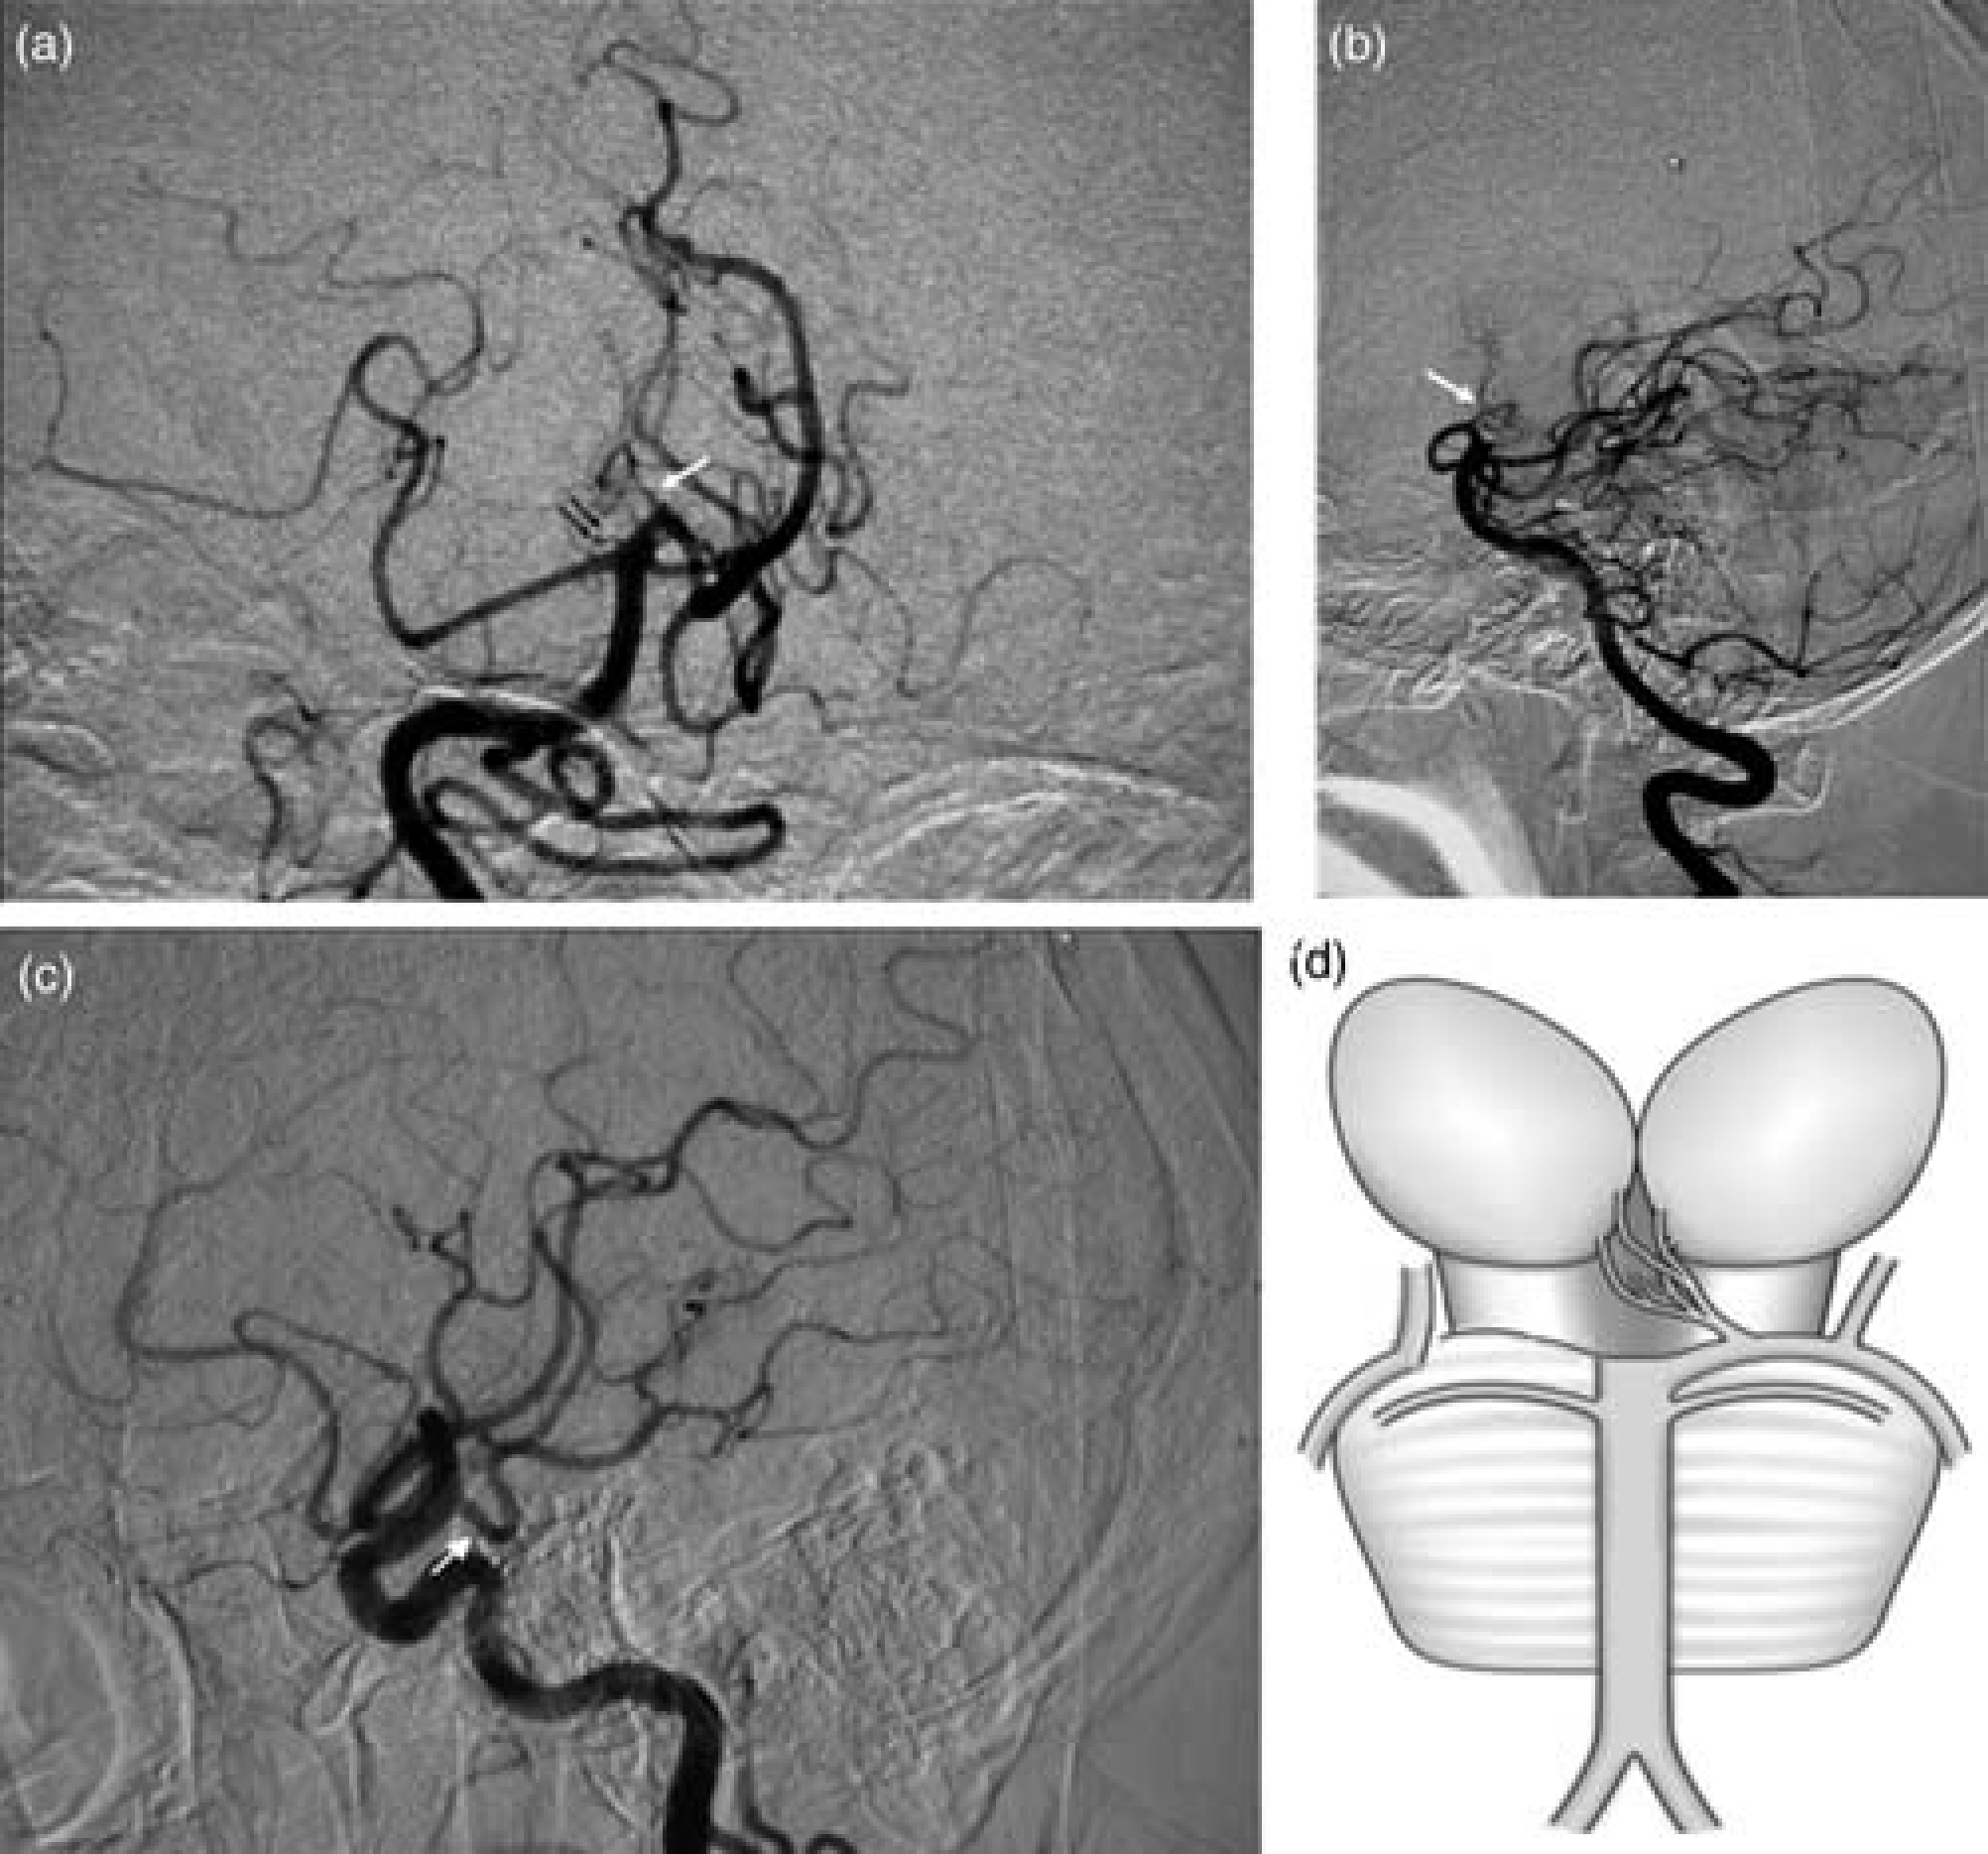

She had no history of diabetes, hypertension, hyperlipidemia, or atrial fibrillation. Laboratory investigations were unremarkable. An MRI after three weeks showed symmetric enhanced signals in the paramedian thalamus (Fig. 1). Digital subtraction angiography (DSA) showed that the P1 segment of the right PCA was absent. The P2 segment was supplied by the right posterior communicating artery (PcomA). A stenotic AOP originated from the left P1 segment was also visualized (Fig. 2).

(a, b) DSA of the right vertebral injection, anteroposterior view (a) and lateral view (b) showed a stenotic AOP originating from the left P1 segment (white arrow). The P1 segment of the right PCA was absent (black double-arrow). (c) DSA of the right carotid artery injection showed the abnormally enlarged right PcomA could be the source of the right PCA (white arrow). (d) A schematic diagram represents a possible new variant of AOP. The P1 segment of the right PCA is absent while the AOP originates from the left

Percheron described three possible variations involving the paramedian thalamic-mesencephalic arterial supply (5). However, the P1 segment and PcomA were not completely evaluated in any of these types. In this case, we demonstrated an AOP variant together with the absence of the contralateral P1 segment. The absence seems more like an anatomic variant than acute occlusion because the right PcomA was abnormally enlarged, indicating that it could be the source of the right PCA. We believe that the presence of AOP combined with the absence of the contralateral P1 could be a new type of anatomic variant which has not been reported before.